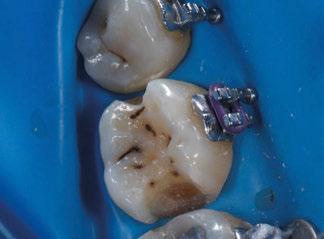

Con el cementado de los brackets de la técnica Universal Smile System

(USS), como se aprecia en las figuras 23 a 25, comienza la segunda fase de tratamiento. Esta duró tan solo 12 meses debido a que gran parte de las relaciones oclusales habían mejorado durante la etapa anterior. Los resultados finales del tratamiento se observan en las figuras 26 a 30 , con la corrección de la clase molar y canina, el resalte y la sobremordida, el centrado de las líneas 1/2 y la curva de Spee. La mejoría en la macro, mini y microestética facial se aprecia en las figuras 31 a 33 , a pesar de la evidente desviación del mentón hacia

Figuras 18-25.